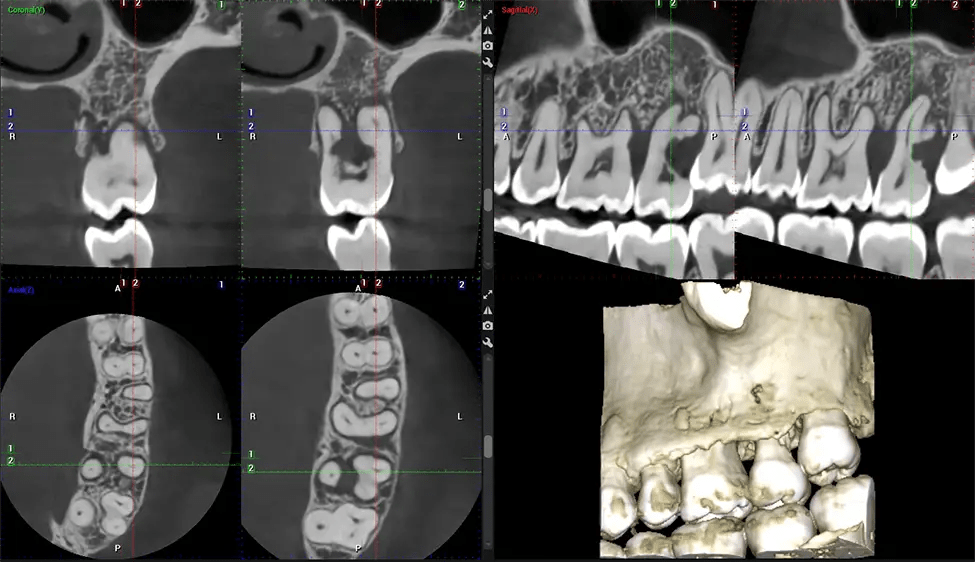

Cone Beam Computed Tomography (CBCT) is an advanced imaging technique used in dentistry and maxillofacial surgery to obtain detailed 3D images of the oral and maxillofacial structures. At Dr G Dental Studio, our CBCT scanners utilize a cone-shaped X-ray beam and a specialized detector to capture images from different angles. A computer then combines these images to create a 3D representation of the patient’s oral anatomy.

This 3D scan, called cone beam computed tomography, gives your dentist a more complete image of your oral anatomy and disease processes than a traditional X-ray. Unlike conventional X-rays, which capture a 2D image of your mouth from various angles, a 3D scan takes multiple digital X-rays for one image. It provides a complete view of your jaw, teeth, nerves, and soft tissues. This enhanced view allows dentists to detect minor issues not visible in traditional 2D scans, such as impacted wisdom teeth or bone fractures in the sinus cavity.

There are many benefits to using CBCT technology, especially compared to the traditional 2D X-ray format. One of the most significant advantages of CBCT scans is that they provide much more information than traditional X-rays. A scan lets your dentist see images from all angles of your jaw and mouth, including your sinuses, nasal cavity, cheekbones, and other surrounding areas. This added information helps your dentist craft a comprehensive treatment plan that addresses all aspects of your oral health.

Another significant benefit is that 3D imaging provides more precise images of your bone structure. These images are more detailed, providing you with a more accurate diagnosis. An accurate diagnosis means better treatment for you.

After the scanning process, the captured X-ray images are processed by the CBCT software, which applies algorithms to reconstruct a detailed 3D image of the scanned area. The software compiles these individual X-ray images and creates a digital 3D representation of the patient’s anatomy. The reconstructed 3D CBCT image can be viewed and analyzed by the dentist or radiologist. This image can be manipulated, rotated, and zoomed in or out to examine specific structures and evaluate the patient’s condition.